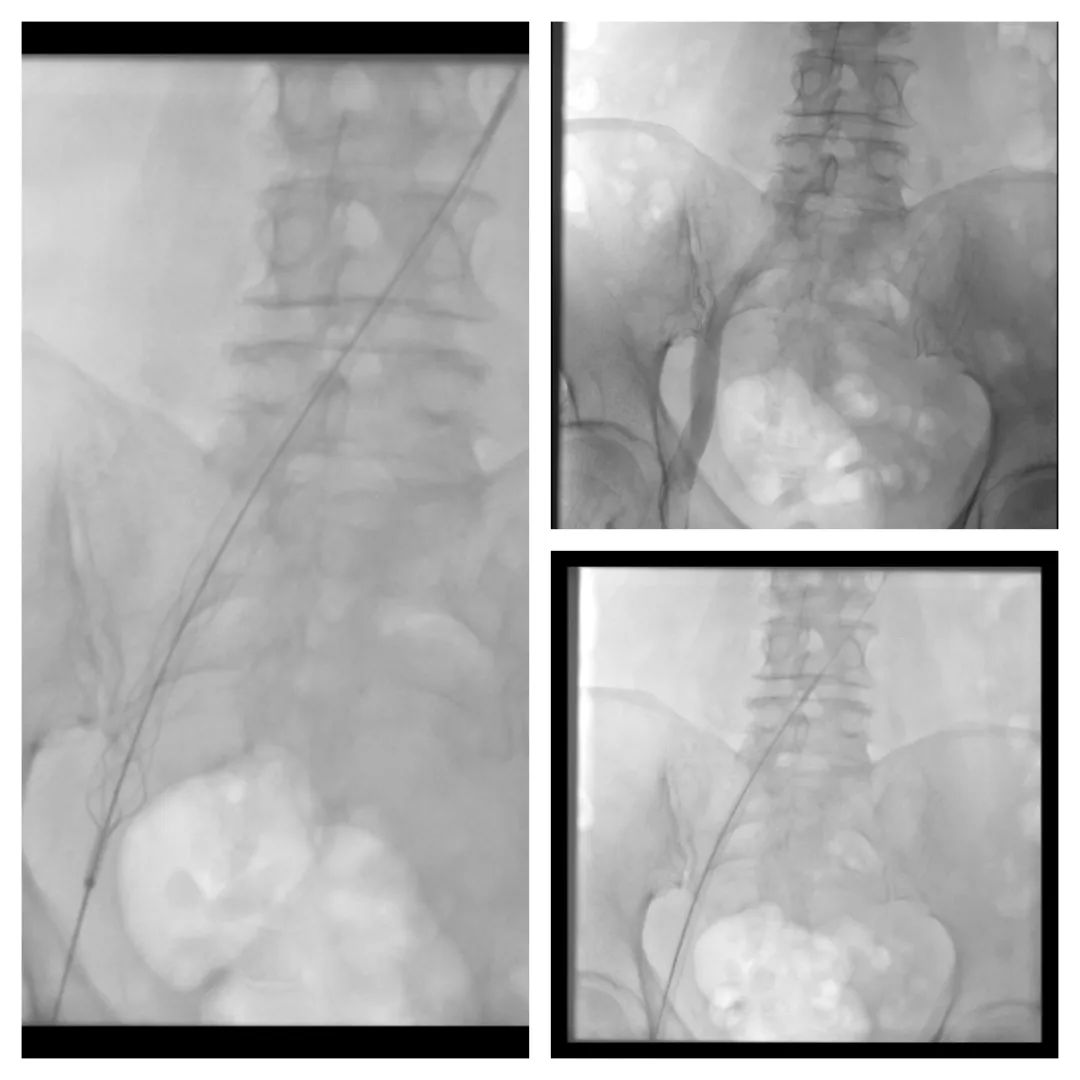

② 引入Tendfast®外周静脉取栓支架,从左侧髂静脉到股静脉、股浅静脉进行3次拉栓,拉出部分血栓。

③ 造影显示左下肢深静脉通畅,拔除腘静脉血管鞘,使用纱布加压固定,返回病房。

术前造影

支架取栓中

术后造影